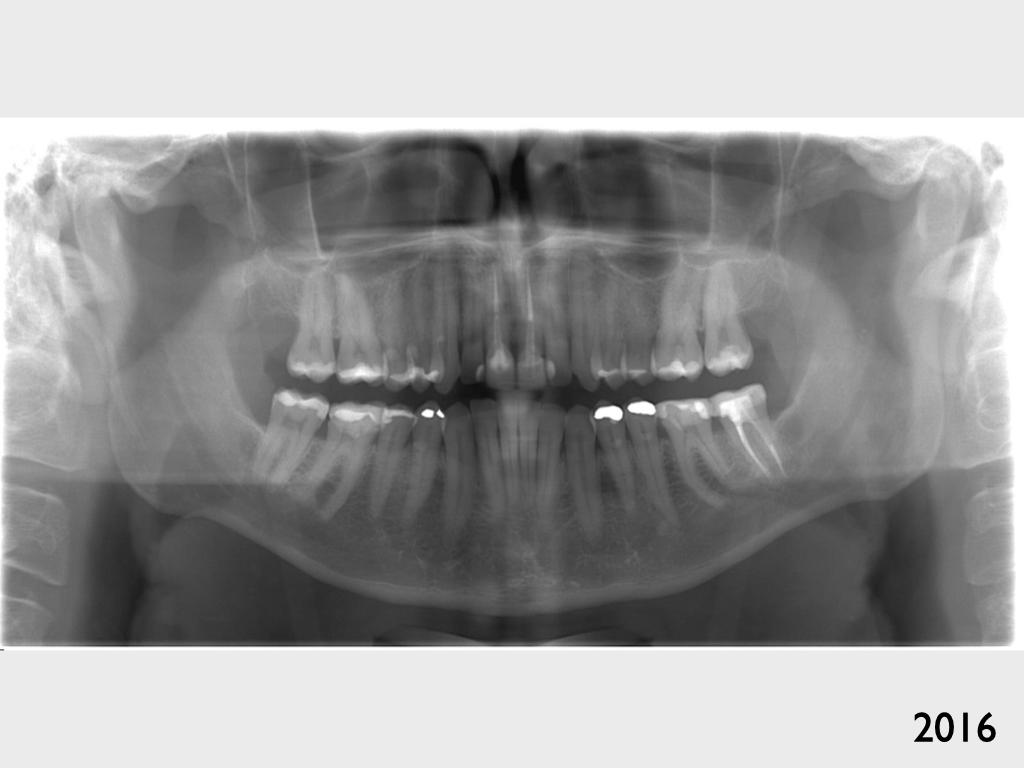

Unklarer Abszess?